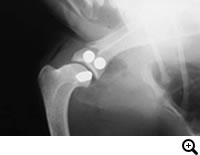

肩関節脱臼

肩関節が外れた状態、内方脱臼と外方脱臼があります。

レントゲン検査

手術をせずに整復し固定をおこなっても治ることが少なく、外科的に脱臼を整復し固定する必要がある場合が多いです。内方脱臼ではスーチャーアンカーを用いて整復する方法など、外方脱臼では二頭筋腱の転移術などを行います。それでも再脱臼する場合、最終的な救済処置として関節固定術を行うこともあります。